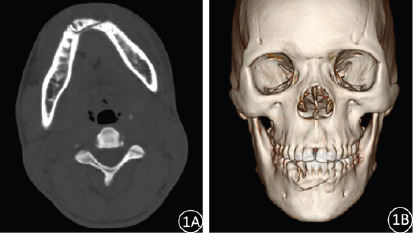

Results: In this study, 52 cases of maxillofacial fractures with a total of 83 fractures were diagnosed by 2D CT reconstruction technology, with a fracture detection rate of 77.61% (52/67). Using 3D CT reconstruction technology, 54 cases of maxillofacial fractures with a total of 91 fractures were diagnosed, and the fracture detection rate was 80.60% (54/67). Statistical analysis showed no significant difference in the detection rate of maxillofacial fractures between 2D CT and 3D CT reconstruction (χ2 = 35.945, P = 0.687). In the diagnosis of zygomatic fractures, nasal fractures, and upper and lower jaw fractures, 3D CT reconstruction images have obvious advantages over 2D CT in displaying fracture displacement and fracture line course. However, for the display of comminuted fractures combined with sphenoid and ethmoid fractures, the cross-sectional images of 2D CT show higher superiority.

Conclusion: 2D CT reconstruction is a basic diagnostic tool for maxillofacial fractures. 3D reconstruction, with high detection and multi-angle visualization, offers valuable imaging for clinical decision-making, aiding in surgery planning. A combined approach, leveraging the strengths of both modalities, is pivotal for comprehensive assessment and management of maxillofacial trauma.